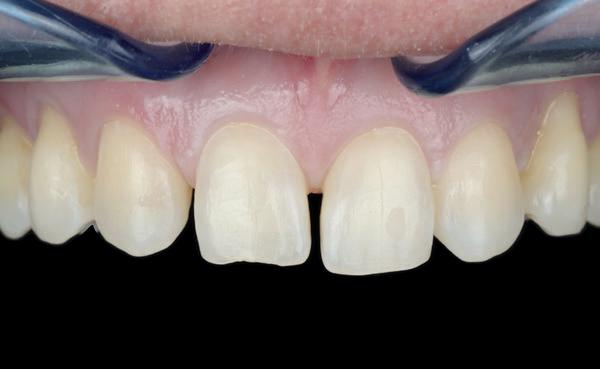

Op 16-jarige leeftijd werd de patiënt door haar behandelend orthodontist naar de auteur verwezen voor een restauratieve oplossing voor de afwezige 11 en 21. In de tussenliggende periode had patiënt een retainer gedragen met twee kunststof tanden (afbeelding 1). Zowel de patiënt als haar moeder hadden een sterke voorkeur voor een implantaat gedragen vaste oplossing. Gezien haar jonge leeftijd was dit echter nog geen optie, omdat er nog verticale groei te verwachten viel. Implanteren op jonge leeftijd – dat wil zeggen vóór het 21e levensjaar – kan resulteren in een infrapositie van het implantaat, omdat de rest van het gebit nog verticaal kan doorgroeien.

1. Retainer met twee frontelementen

3. Vaste apparatuur voor torque 12 en 22

5. Beginsituatie voor behandeling